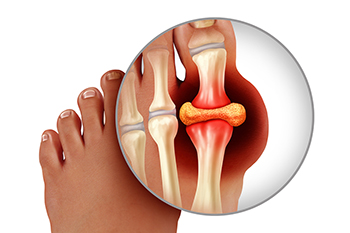

Gout is a type of arthritis caused by a buildup of uric acid crystals in the joints, often affecting the big toe, but also the foot and ankle. Symptoms include sudden, severe pain, redness, swelling, and warmth in the affected joint, making walking or standing difficult. Risk factors include a diet high in purines, obesity, genetics, alcohol consumption, and certain medical conditions. Repeated gout attacks can lead to joint damage, decreased mobility, and long-term discomfort. A podiatrist can diagnose gout, recommend lifestyle adjustments, prescribe medication, and provide care to reduce pain and prevent future attacks. Early intervention helps protect joint health and improve mobility. If you have gout symptoms in your big toe or foot, it is suggested that you promptly consult a podiatrist who can help you to manage this painful condition.

What Is Gout?

Gout is a form of arthritis that is characterized by sudden, severe attacks of pain, redness, and tenderness in the joints. The condition usually affects the joint at the base of the big toe. A gout attack can occur at any random time, such as the middle of the night while you are asleep.